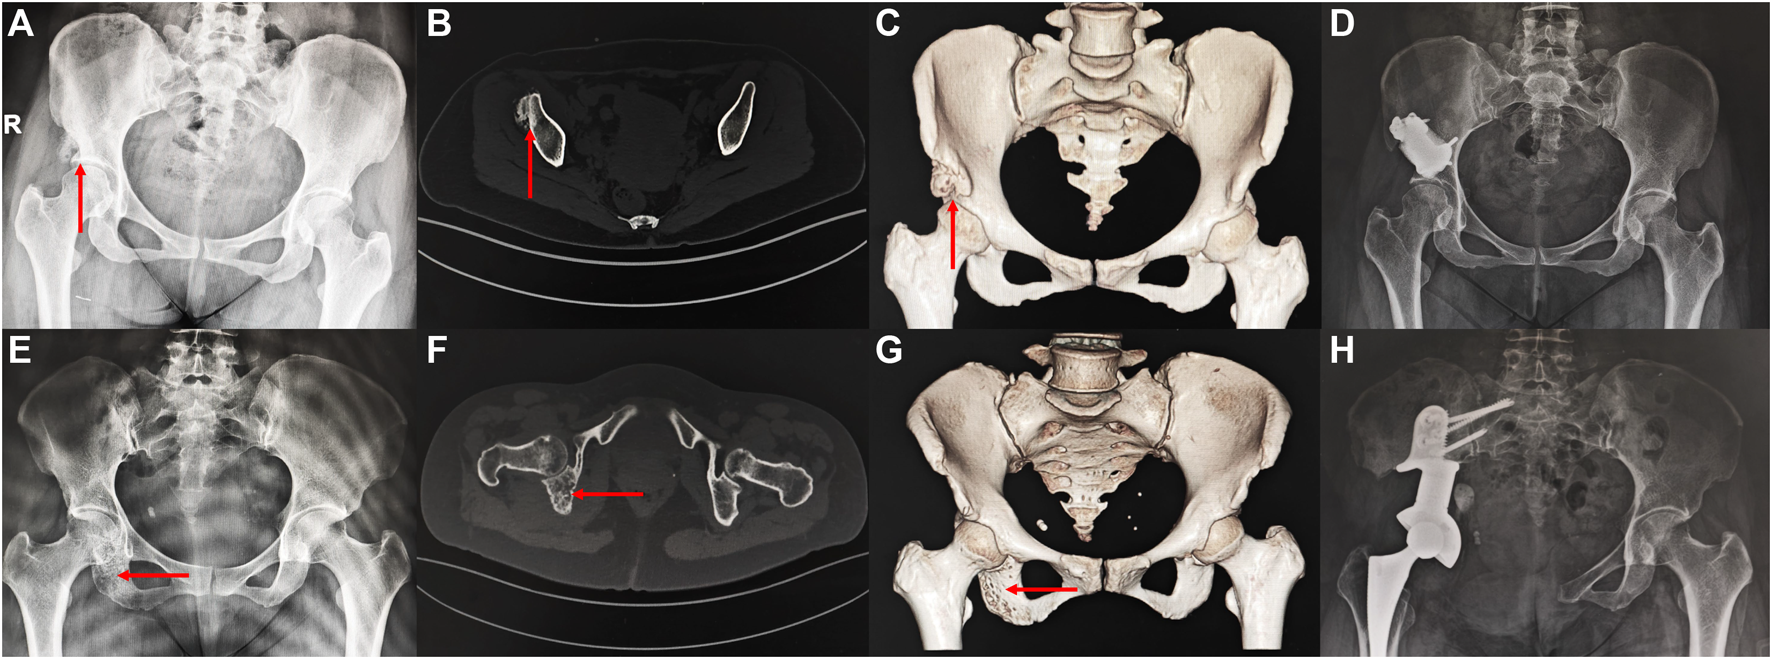

The information about the two patients is shown in Figure 6. Both patients achieved primary wound healing within 2 weeks without any major complications. However, the patient who underwent Type-I prosthesis reconstruction experienced numbness of the lateral cutaneous nerve of the thigh as a postoperative complication related to the surgical approach. The length of hospital stay for Type-I prosthesis reconstruction was 7 days, while it was 16 days for Type-II prosthesis reconstruction. The time needed for out-of-bed ambulation after surgery was 24 days for Type-I prosthesis reconstruction and 36 days for Type-II prosthesis reconstruction. The follow-up period was 36 months for Type-II prosthesis reconstruction and 15 months for Type-I prosthesis reconstruction. By this time, both patients had returned to their daily work, and their MSTS scores at the 12th month after surgery were both 100% (Supplement Materials).

FIGURE 6. Imaging of the patient preoperatively and postoperatively (A–D) a 46 years old female patient diagnosed with osteoidostema; (E–H) a 49 years old female patient diagnosed with leiomyosarcoma.